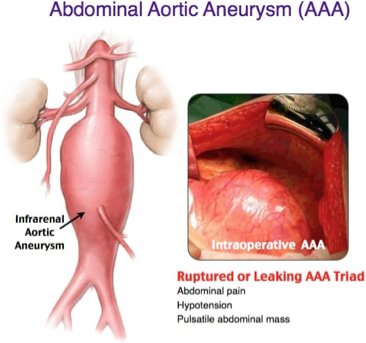

Abdominal (aortic aneurysm) (AAA)

Often asx until dissection begins

Abdominal/chest pain and back pain

“Gnawing, ripping or tearing” abdominal pain

Compression of nerve roots

Associated sx:

Anxiety

N/V

Clammy skin

Tachycardia

Clinical history of aortic aneurysm

May be incidental on rad scans

Palpable, pulsatile abdominal mass

May be palpable as a pulsatile mass (AAA)

Bruit may be heard from turbulent blood flow (AAA)

“Gushing noise”

BP May be elevated followed by a sudden Hypotensive episode

What does this refer to

Abdominal pain

Hypotension

Pulsatile abdominal mass

Ruptured or leaking AAA “triad” Aortic Aneurysm